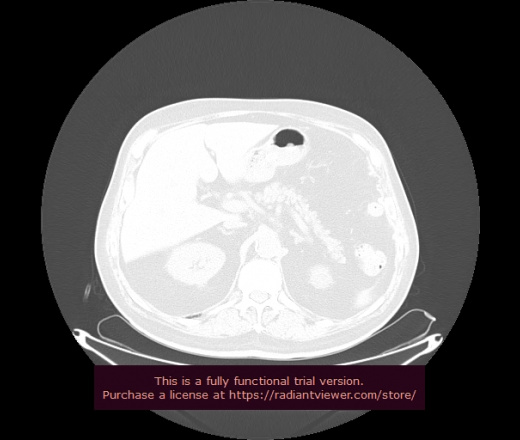

Уважаемые коллеги, если имеется интерес, сможете ли Вы спрогнозировать дальнейшее +-одинаковое течение процесса у 4 данных разных пациентов? Зацепиться где-то можно очень просто, где-то нельзя.